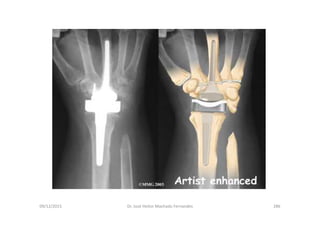

Artroplastia do Punho

Componentes da artroplastia do punho